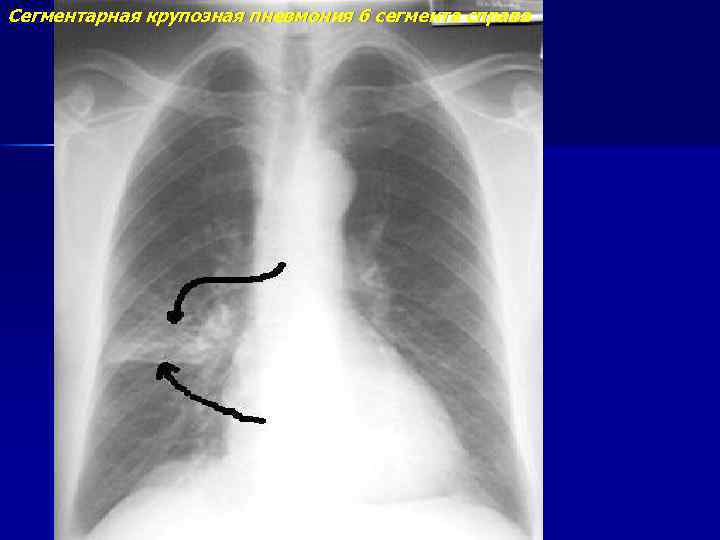

Сегментарная крупозная пневмония 6 сегмента справа